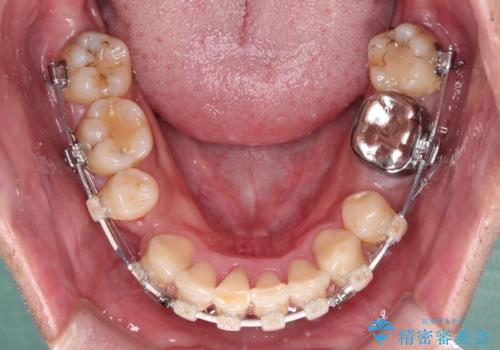

- 矯正装置

- 審美装置

第二小臼歯抜歯の矯正治療は、治療期間が長引くことが多いですが、動きが非常に良く、予定の治療期間で終えることができました。

上下の正中も思っていた以上に良い位置に改善されました。